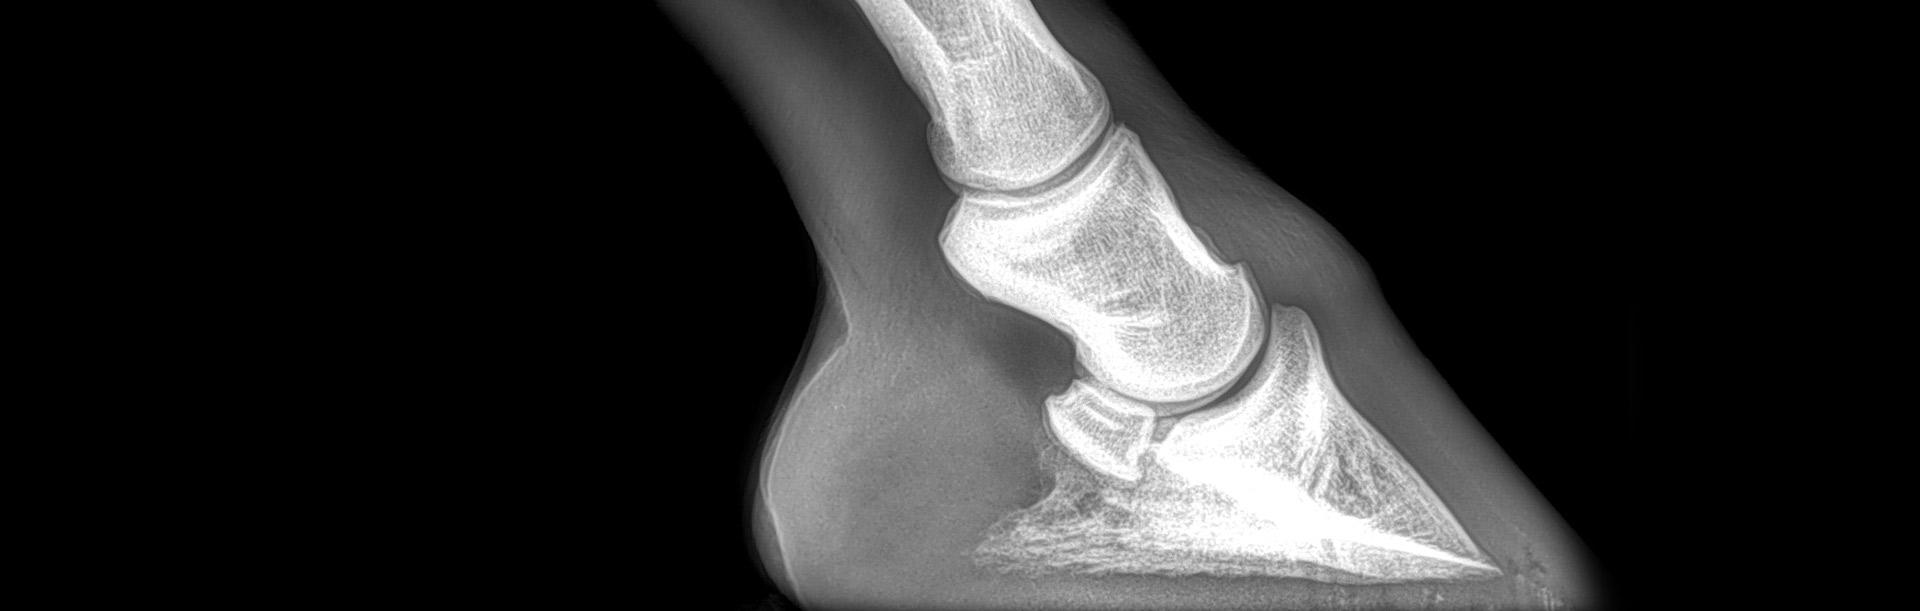

Radiología

Contamos con el equipo de radiología digital inalámbrico más avanzado del país, el cual permite obtener las mejores imágenes en el acto y compartirlas vía mail. Realiza radiografías de miembros, columna, cabeza, cuello y hombro.